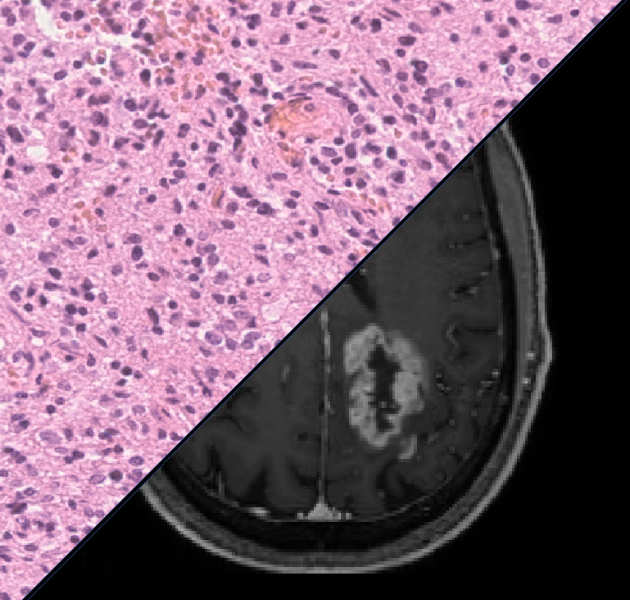

Brain tumour biomarker development

We are investigating imaging biomarkers (diffusion MRI, perfusion MRI, MR Spectroscopy, choline PET) and developing the clinical tools needed to understand brain tumour growth and improve brain tumour diagnosis.

We are investigating imaging biomarkers (diffusion MRI, perfusion MRI, MR Spectroscopy, choline PET) and developing the clinical tools needed to understand brain tumour growth and improve brain tumour diagnosis.

Brain tumour classification through machine learning

We are developing new machine learning tools to aid clinicians in diagnosing brain tumours through MRI and digital pathology.

We are developing new machine learning tools to aid clinicians in diagnosing brain tumours through MRI and digital pathology.